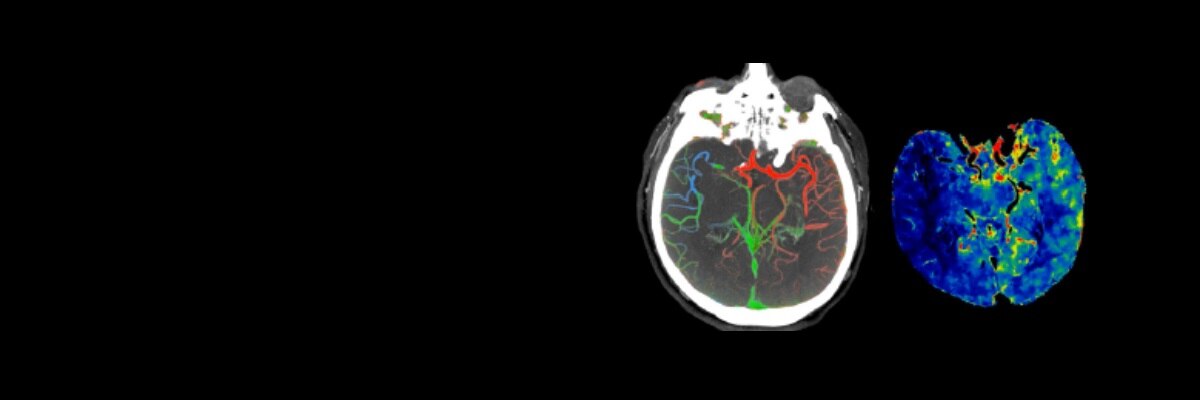

SOLUZIONI PER L'ICTUS